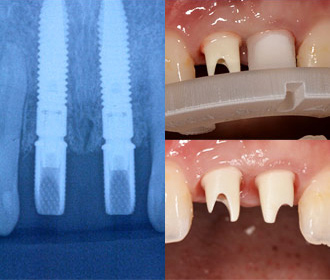

インプラント2次治療後、歯周組織移植などを行い、歯間乳頭が再生された。

-

アトランティスシステムにより、ジルコニアアバットメントがCAD/CAMにより作製された。

アトランティスのガイドにより正確に位置決め可能。 -

ジルコニアアバットメント上に装着されたプロビジョナル、矯正治療は継続。

矯正治療、骨移植を伴うインプラント治療、セラミック・クラウン等による機能的、審美的治療

矯正治療、骨移植を伴うインプラント治療、セラミック・クラウン等による機能的、審美的治療

術前